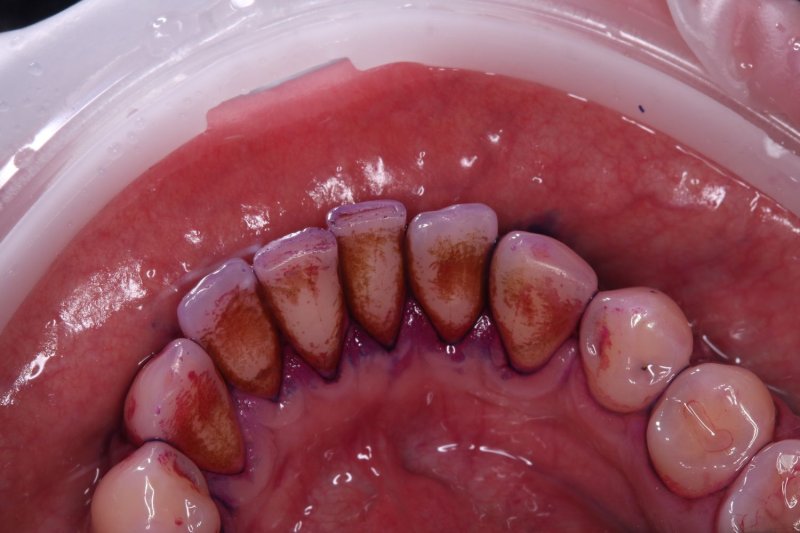

До

udalenie-naleta-ot-kureniya-gbt-do

Наличие мягких и твердых зубных отложений, осложненных стойким эстетическим дефектом — пигментированным налетом от курения и употребления кофе, который не удаляется обычной щеткой.